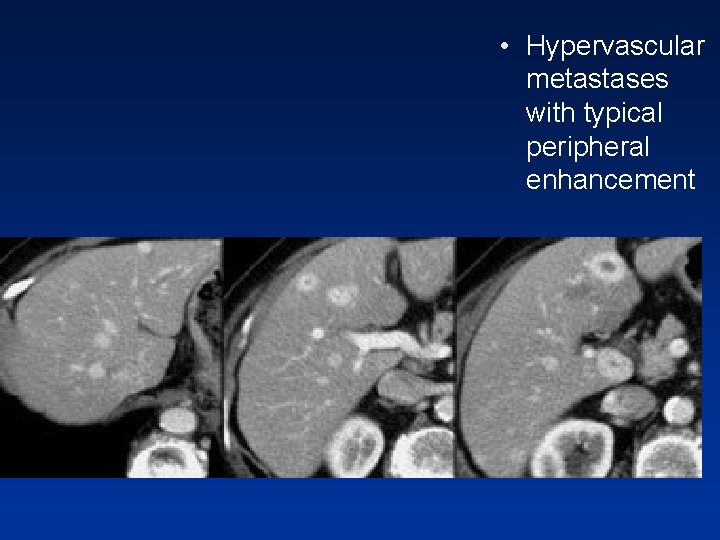

• Hypervascular metastases with typical peripheral enhancement

• Peripheral enhancement in metastases from breast carcinoma